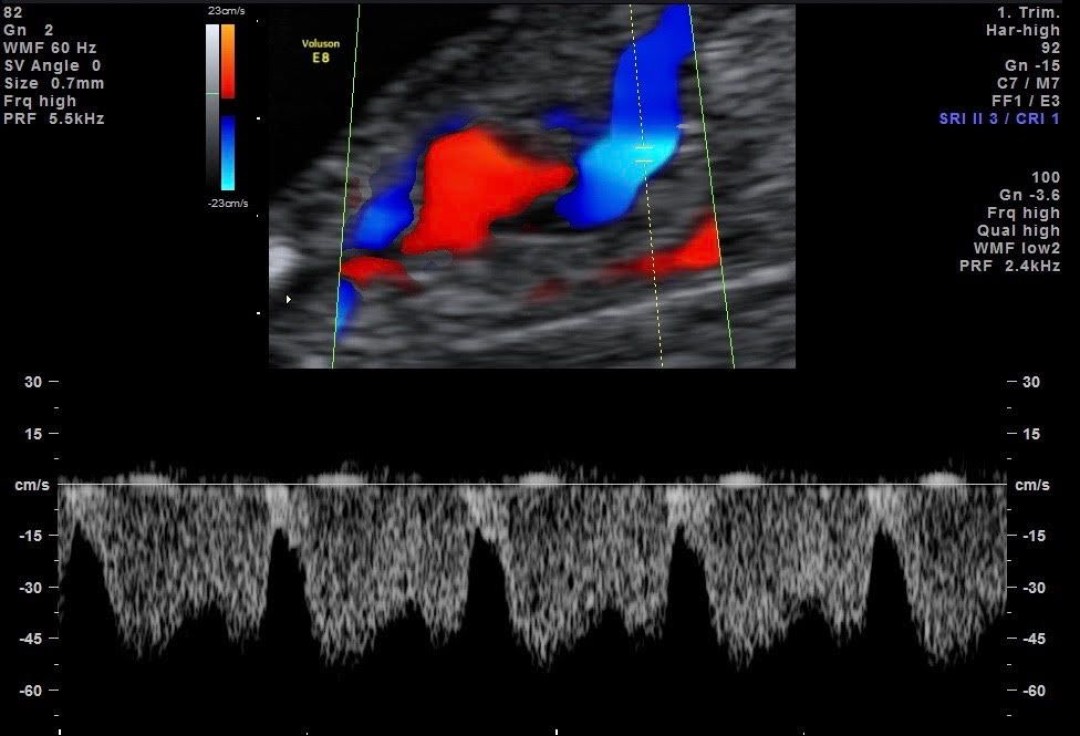

Ukoronowaniem zainteresowań była rozprawa doktorska poświęcona ocenie układu krążenia matczynego i płodowego w przypadkach ciąży powikłanej nadciśnieniem tętniczym (2008) oraz akredytacje The Fetal Medicine Foundation (FMF)- najważniejszej europejskiej instytucji certyfikującej i nadzorującej specjalistów zajmujących się diagnostyką prenatalną. Posiadam certyfkaty umiejętności Sekcji Ultrasonografii Polskiego Towarzystwa Ginekologicznego w zakresie Diagnostyki Prenatalnej oraz badań serca płodu oraz licencje Fetal Medicine Foundation (FMF) dot. przeprowadzania ultrasonograficznych badań płodu między 11 a 14 tygodniem ciąży, 20-22 tygodniem ciąży, badań serca płodu czy badań dopplerowskich w ciąży.

Moje zainteresowania kardiologią prenatalną zostały uwieńczone uzyskaniem certyfikatu umiejętności badania serca płodu Sekcji Echokardiografii i Kardiologii Prenatalnej Polskiego Towarzystwa Ultrasonograficznego, z którego bardzo się cieszę. Wspomnę, że jest dla mnie niewątpliwym wyróżnieniem występowanie w roli prelegenta w konferencjach organizowanych przez Sekcję oraz

Możliwość połączenia świata perinatologii, diagnostyki prenatalnej i kardiologii prenatalnej są niezwykle cenne i gwarantują kompleksowość konsultacji.

Wysoką jakość wykonywanych badań gwarantują Państwu liczne ukończone krajowe i międzynarodowe kursy z zakresu diagnostyki wad płodu, ciąży wielopłodowej, echokardiografii płodowej, zaawansowanych technik dopplerowskich w położnictwie i ginekologii oraz kolejne, od kilkunastu lat pozytywnie ocenione audyty FMF w zakresie badań płodu między 11+0 a 13+6 tygodniem ciąży.